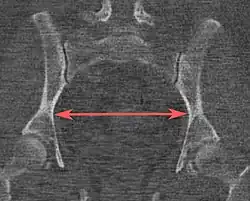

Interspinous distance | ![]() |

The line between the closest bone points of the ischial spines | 9.5 to 11.5 cm.[6] | |